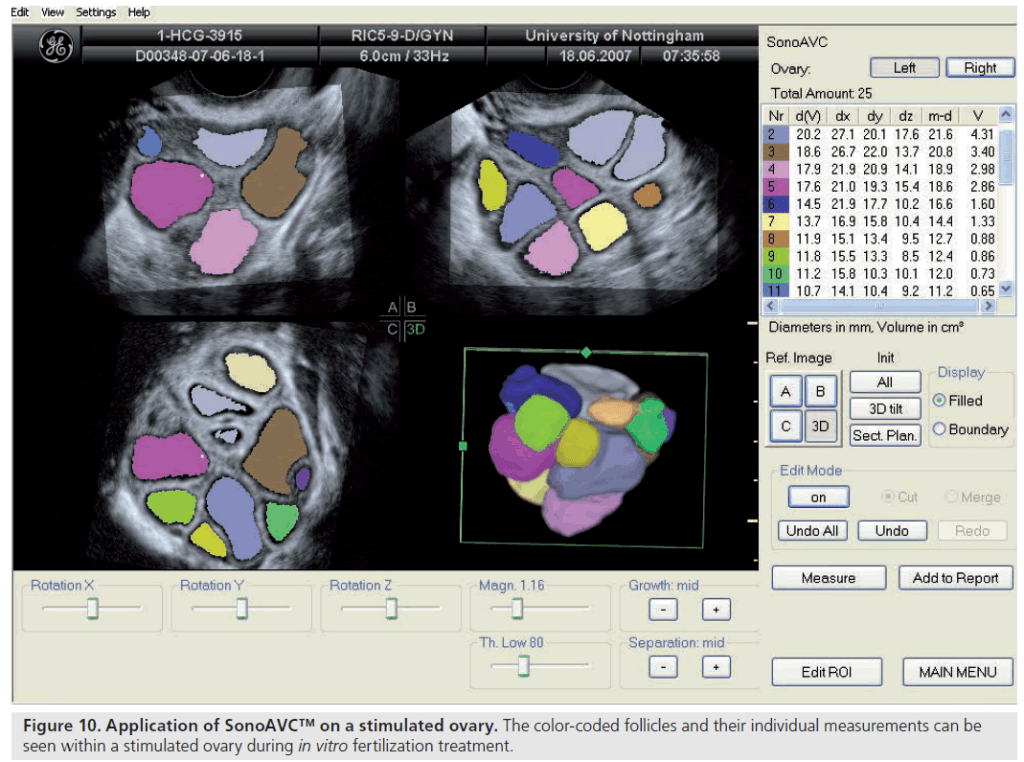

Entre os métodos ultrassonográficos disponíveis, considera-se a contagem de folículos antrais (AFC) o marcador mais confiável para estimar a reserva ovariana.

Realizada por meio de ultrassonografia transvaginal, ela quantifica os folículos de 2 a 10 mm presentes em ambos os ovários, podendo ser feita em 2D ou 3D. As tecnologias tridimensionais e as ferramentas automatizadas, como o SonoAVC, oferecem medições mais precisas e reprodutíveis.